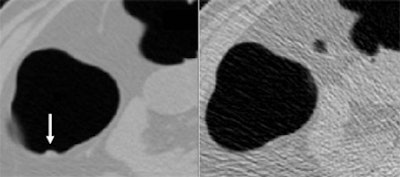

| A 10-mm polyp at the splenic flexure. The polyp is visible in both low-dose (upper left) and standard-dose (upper right) CTC images. CAD detected the polyp in both doses (lower left and right). Images courtesy of Dr. Masanori Imuta and Dr. Hiro Yoshida. |

CAD's by-polyp sensitivity for polyps of all sizes was 83.3% for standard dose studies and 77.8% for ultra-low-dose exams, with an average of four false-positives per patient. With CAD, the three readers’ average sensitivities for standard- and low-dose studies were 100% and 88.9% (≥ 10 mm), and 78.8% and 60.1% (< 10 mm), respectively, with an average 2.3 false-positives per study.